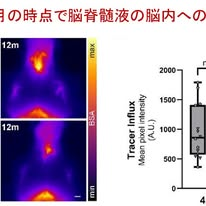

研究では,ヒトのADに近い病態を再現するApp knock-inマウスが用いられました.これはヒトの家族性ADで見つかったAPP遺伝子変異を,マウス自身のAPP遺伝子の位置にそのまま組み込んだモデルマウスです.特に,Aβ蓄積が比較的ゆっくり進むAPPNL-Fマウスと,急速にプラークが形成されるAPPNL-G-Fマウスを比較することで,病態の時間的変化を解析しました.

最も重要な結果は,グリンファティック機能低下がアミロイドプラーク形成よりも早期に起こるという点です.図1では,脳脊髄液に蛍光トレーサーを注入して脳内への流入を評価しています.その結果,APPNL-Fマウスでは6か月齢の段階で既に流入が低下していることが示されました.しかし同時期には,脳実質におけるAβプラークはまだほとんど形成されていません.つまり,ADでは「Aβが溜まるから排水が悪くなる」のではなく,排水システムの障害が先に起きている可能性が示されたわけです.さらに基底核にトレーサーを直接注入して48時間後の残存量を評価すると,APPNL-Fマウスではトレーサーが多く残存しており,排出機能も低下していることが確認されました(図2).

以上の結果をまとめるとgraphic abstract(図4)のようになりますが,6か月齢のAPPNL-Fマウスでは脳実質のAβプラークはまだ少ないが脳脊髄液中のAβが高く,それがPBM数減少をもたらし,結果としてグリンファティック機能が低下するということになります.

本研究の重要なメッセージは,ADの初期病態として脳脊髄液中AβによるPBM障害とグリンファティック機能低下が存在する可能性を示した点です.AD研究はこれまで「Aβ沈着」を中心に進んできましたが,本研究はその前段階でグリンファティック機能が低下すること,沈着しているAβを除去してもその改善は見られない可能性があることを示した点でインパクトがある研究だと思いました.